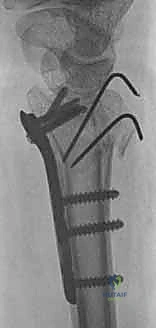

ثانياً: العلاج الجراحي (Surgical Intervention)

متى يقرر الدكتور هطيف ضرورة التدخل الجراحي؟

1. عدم الاستقرار (Instability): إذا كان المفصل الزندي الكعبري البعيد (DRUJ) غير مستقر بعد تثبيت كسر الكعبرة.

2. الانزياح (Displacement): إذا كان الكسر في قاعدة الناتئ الإبري منزاحًا بأكثر من 2 ملم.

3. الكسور المفصلية: أي كسر يخل بتطابق السطح المفصلي لرأس الزند.

4. الكسور المفتتة: في الجزء الكردوسي التي تؤدي إلى قصر عظم الزند.

التخطيط الجراحي لكسور الزند

خطوات التدخل الجراحي الدقيق مع الأستاذ الدكتور محمد هطيف

تُعد جراحات المعصم والزند من الجراحات الدقيقة التي تتطلب مهارة عالية، وهو المجال الذي يتفوق فيه الأستاذ الدكتور محمد هطيف بفضل استخدامه لتقنيات الجراحة المجهرية (Microsurgery) والأدوات الجراحية ذات التقنية العالية.

1. التخطيط ما قبل الجراحة (Pre-operative Planning)

يقوم الدكتور هطيف بدراسة الأشعة المقطعية ثلاثية الأبعاد بدقة، ويختار نوع وحجم الصفائح المعدنية (Plates) والمسامير (Screws) المناسبة لكل مريض بناءً على حجم العظم ونوع الكسر.